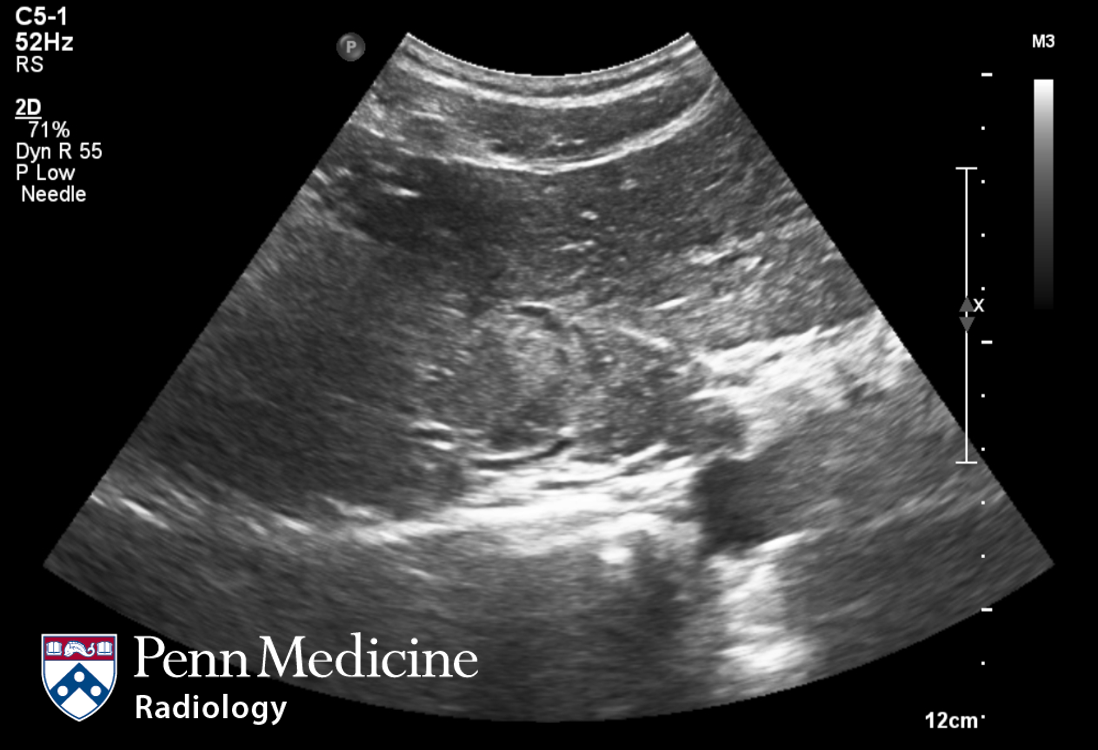

Lesson 1 of 0 In Progress Ultrasound image Ultrasound-guided biopsy was performed. Ultrasound revealed that the lesion had hyperechoic, isoechoic, and hypoechoic parts relative to the surrounding liver. Pathologic diagnosis: angiomyolipoma